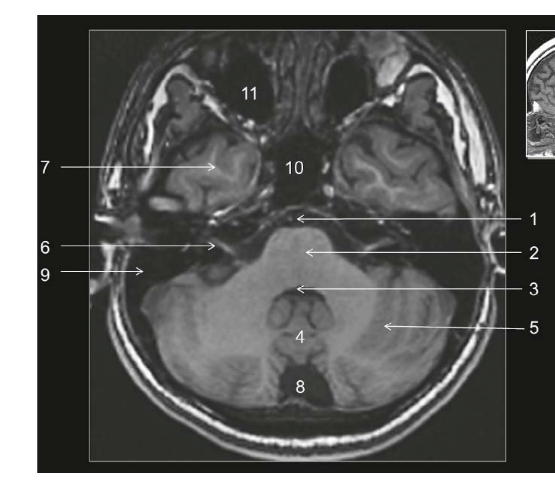

Coupe ?

Légende ?

Coupe ? Légende ?